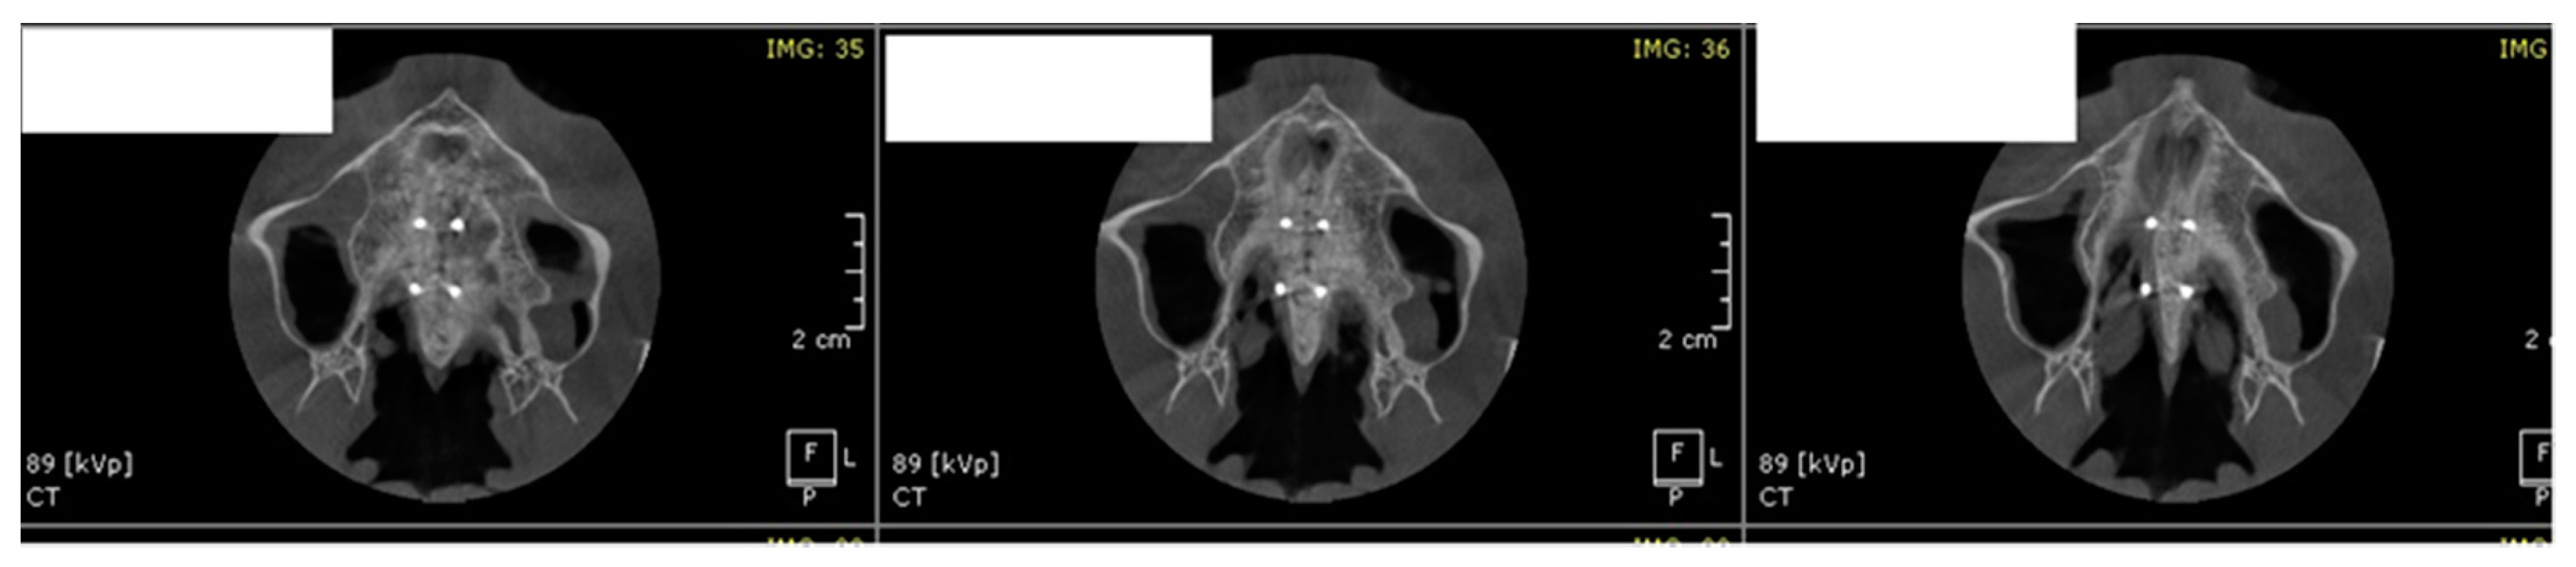

- MARPE associated with cortico-puncture therapy efficiently split the midpalatal suture in adults. The mean split at the anterior nasal spine (ANS) and posterior nasal spine (PNS) was 3.76 and 3.12 mm, respectively. The magnitude of the split at the PNS was smaller than at the ANS (by approximately 85% of the distance), showing that the opening of the midpalatal suture was almost parallel in the anteroposterior direction.

- MARPE therapy associated with cortico-puncture therapy had a positive outcome on midpalatal suture opening and maxillary advancement, but a medium molar inclination of 2.005° was also observed, suggesting that tooth movement cannot be avoided because of the anchorage of the MARPE device at the molar level.

| Mean | 3.766 | 3.125 |

| SD | 0.4956 | 0.4070 |

| Standard error of mean (SEM) | 0.1108 | 0.09102 |

| Lower 95% CI of mean | 3.534 | 2.934 |

| Upper 95% CI of mean | 3.998 | 3.316 |